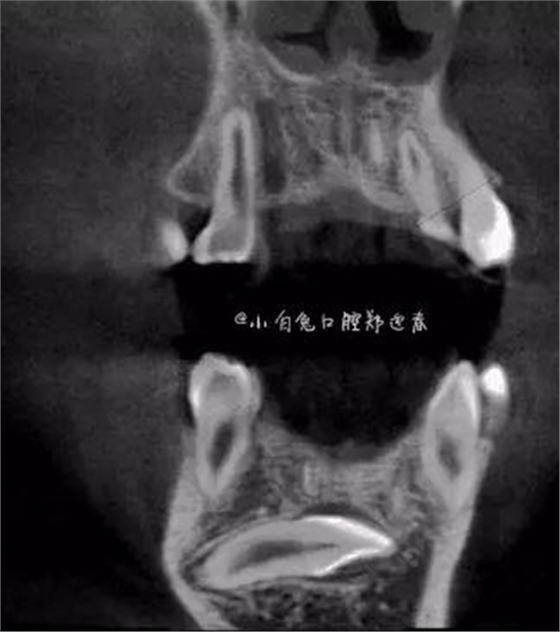

本案:患兒,女,14歲,因牙齒矯正來院,檢查見83滯留,43未見萌出,拍片發(fā)現(xiàn):43埋伏阻生于31、41、42根尖下方,按照正畸診療計劃,擬行43拔除術。

CBCT顯示